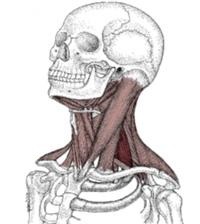

Ez a reakció jellemző bizonyos testrészekre. Különösen előfordul a következő izmok:

- atlasz-gerinces (különösen inferior ferde);

- sacrospinous;

- létra;

- felső részei a trapéz;

- sternoclavicular-mastoid;

- semispinalis és megosztjuk;

-Izomzati tónusos nyaki gerinc szindróma hozzájárul a kialakulásához kedvező feltételek kialakítása a klinikai alagút komplex. Ez kíséri stimulálása neuro-vaszkuláris kötegeket, és a megsértése vezetőképes típusú nervus ulnaris beidegzés. Jellemzően a rendellenesség egyoldalú. A kiterjesztés és forgatás a fej fájdalom intenzitása növekszik. A görcs alsó ferde szálak jellemző a megnövekedett megnyilvánulások a fejmozgató axiálisan a jobb és a bal. -Izomzati tónusos nyaki szindróma gyakran kíséri irritációt az occipitalis ideg és görcsöt az artéria.